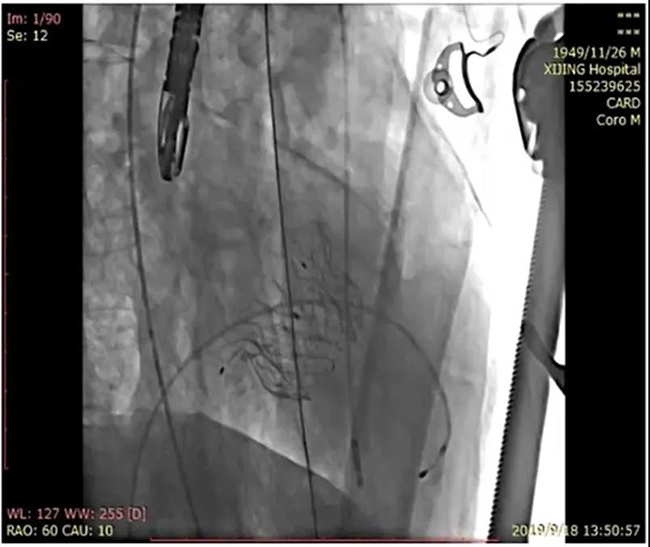

As a leading enterprise in valve industry, especially in the field of mitral valve, Newcastle Medical Co., Ltd. was founded with the mission of "innovation for life", deeply distributed valve field, accurately identified clinical needs, and focused on research and development plan of national 13th five year plan and action plan of scientific and technological innovation of Shanghai Municipal Science and Technology Commission - production, study, research and research Under the framework of "research and development of new type of mitral valve replacement system and achievement transformation" of medical cooperation project, the combination of deep cultivation and medical engineering has successfully developed Mi thos ® Transcatheter mitral valve replacement system (MI thos) ®”)。 Mi-thos ® The system is to transfer the valve to the mitral valve area and expand it after the small incision of the apex, which replaces the lesions of the mitral membrane. Traditional thoracotomy usually takes four to five hours, while Mi thos ® The system can complete valve implantation in just one hour. Mi-thos ® The system is designed according to the pathological anatomy of Chinese people. The innovative design concept of "rigid and flexible" internal and external double-layer stent is adopted to care for the Chinese "heart". Mi-thos ® The D-shaped structure of the outer frame can effectively fit the physiological structure of the mitral valve, and the sealing membrane is used to prevent the leakage around the valve. The unique three-layer barb anchoring structure can effectively prevent valve displacement and improve the safety of operation.